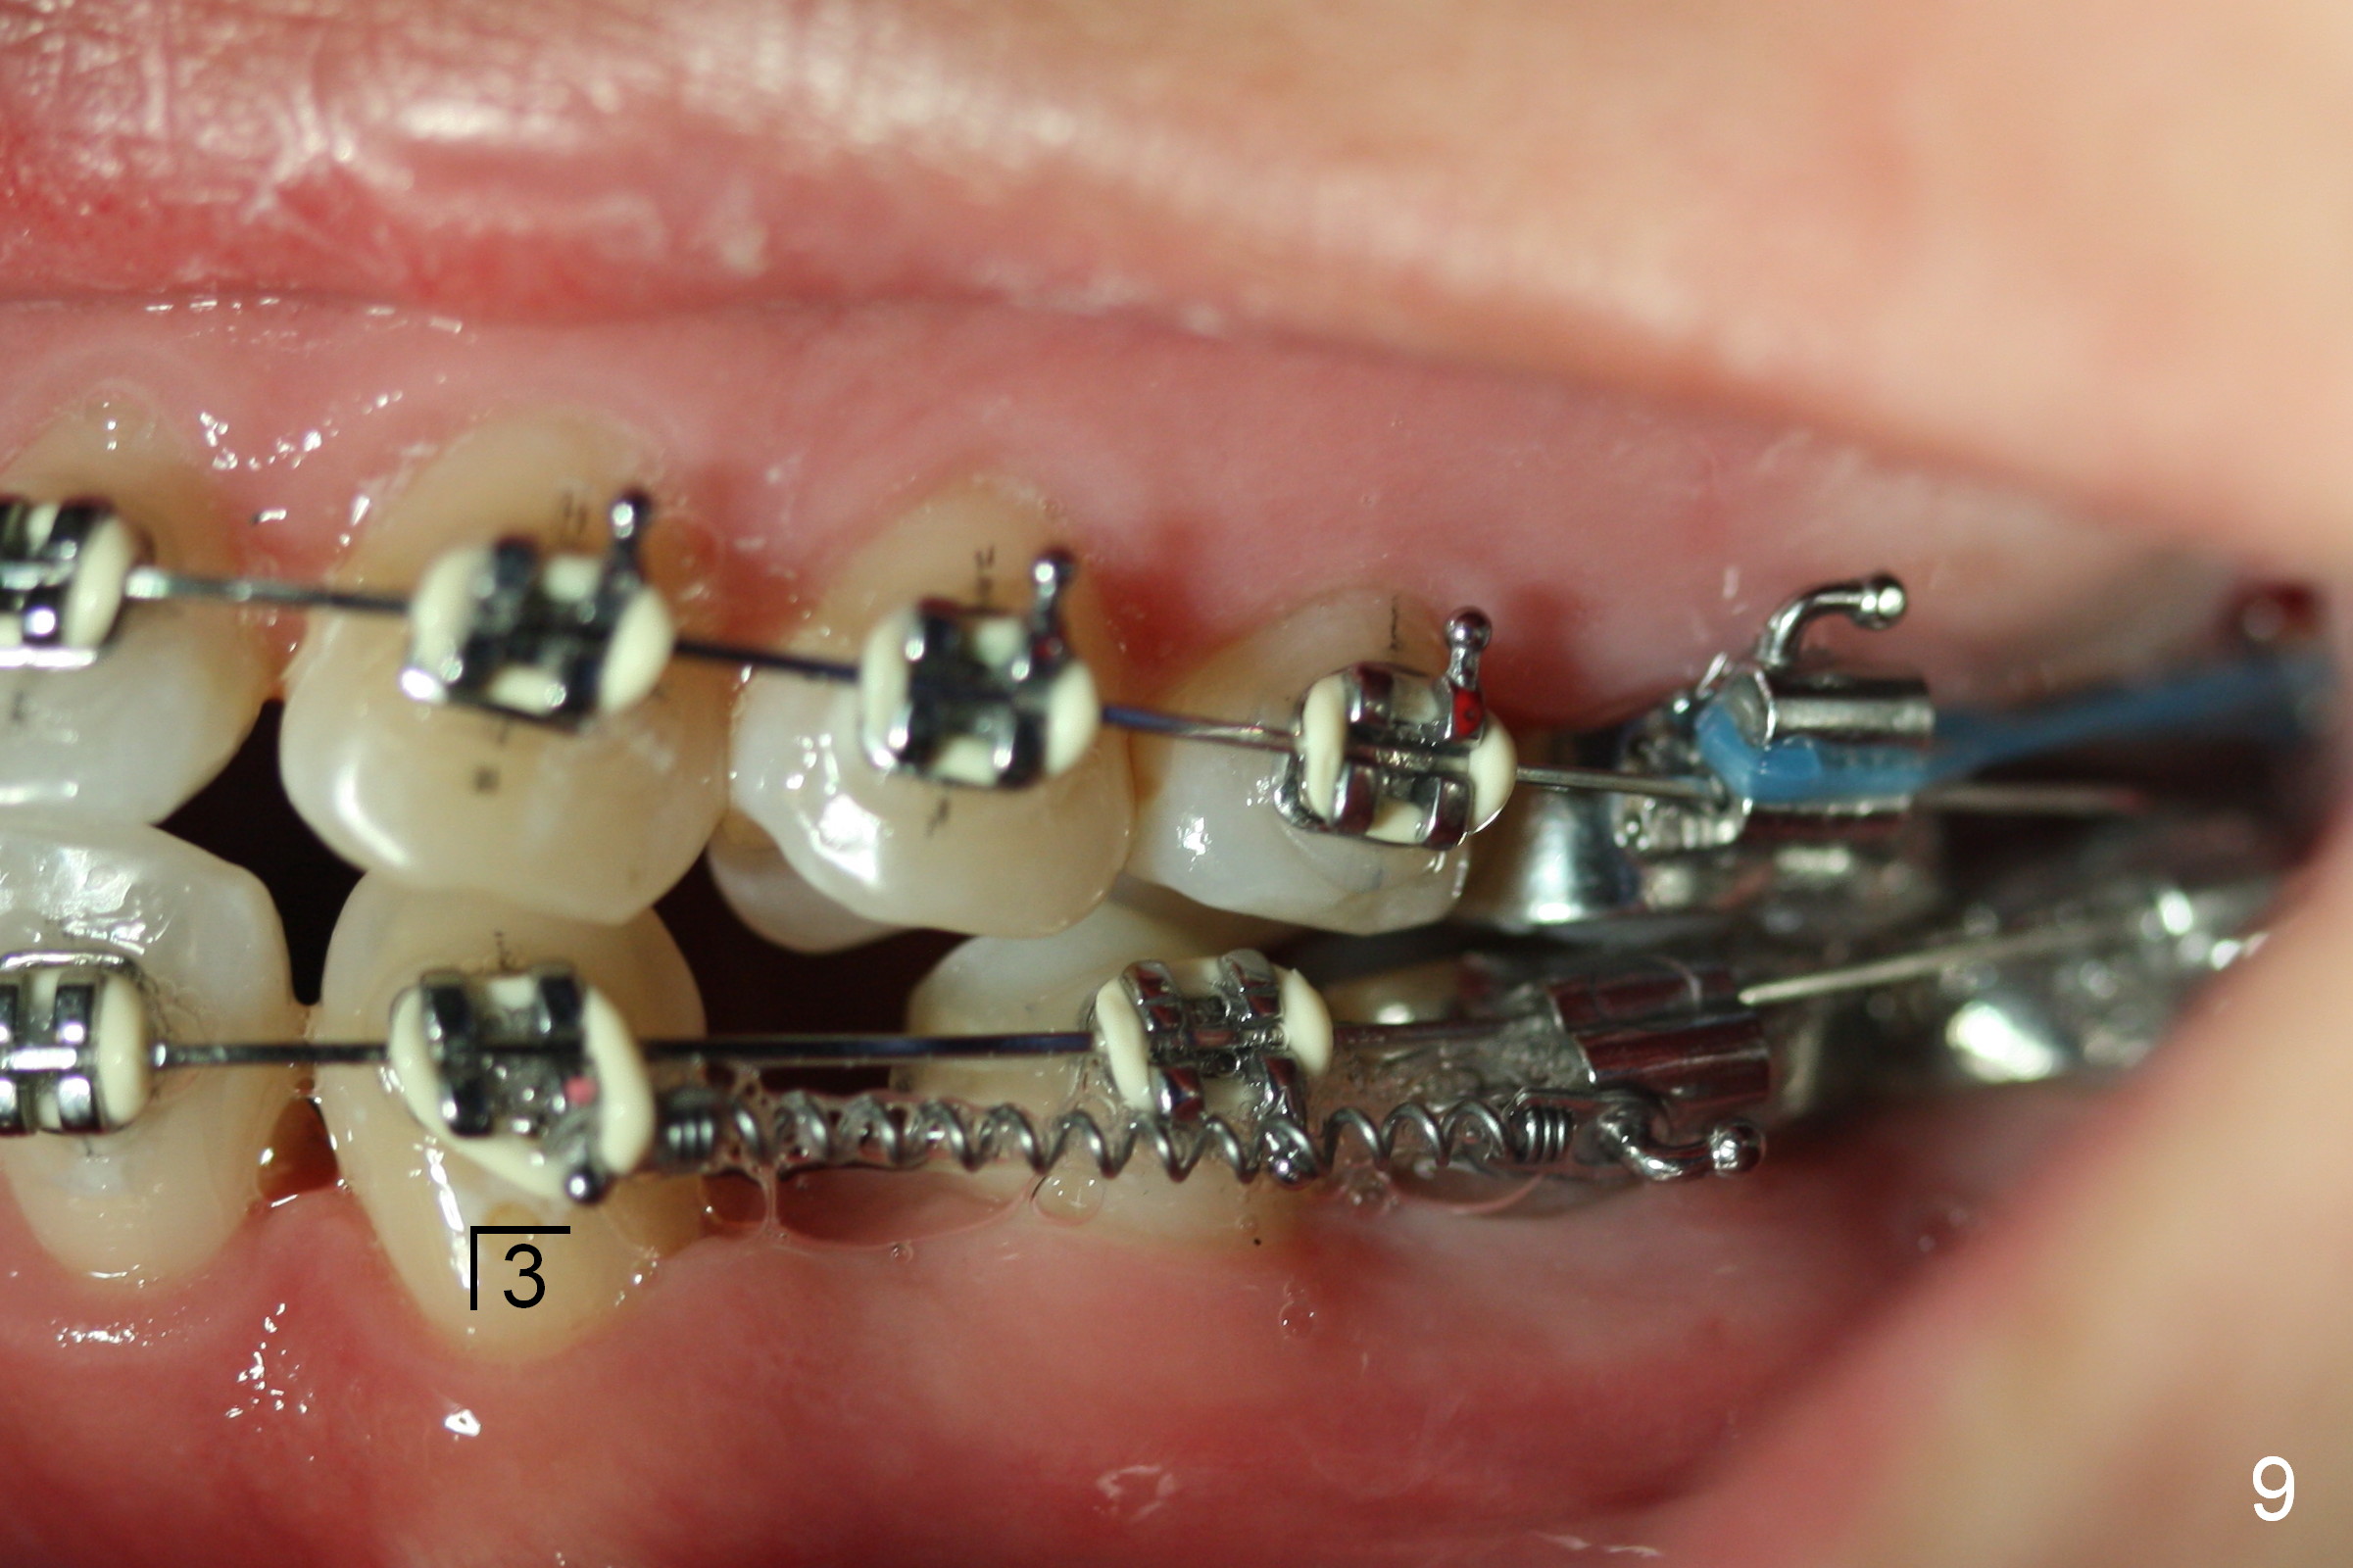

Four months post bracketing, two of 8 mm Ancor Mini-implants are placed at the sites of the upper 2nd molars and power chain of 3 placed between the 1st molars and the mini-implants (Fig.6,8). Niti Closing Springs (12 mm and 9 mm) are placed between LR4 and 7 and LL 3 and 6, respectively (Fig.7,9, 16x16 ss wires). The forces are 100 and 150 mg, respectively.

Two weeks later, it appears that U3s do not move distal (Fig.10,12), whereas the lower teeth do (Fig.11,13). Power chains change to 2 with grey ones. If no more change occurs in 1 week, change to next wires with power chains x 4 with one end attached to the lingual cleat (Fig.10,12 arrowheads) so that U3s may evenly (buccal and palatal) move distal. If LL3 keeps moving much faster than LR4, switch the closed coil springs.